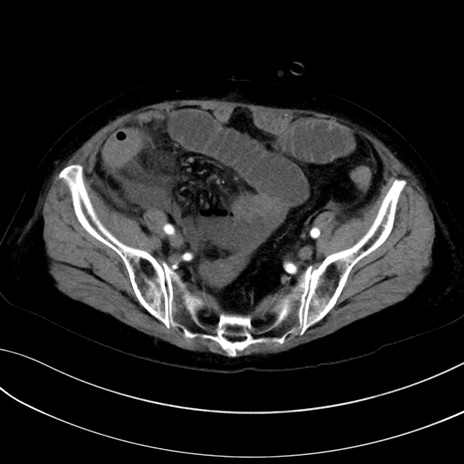

症例13 CT(横断像)1日半後

(冠状断像)1日半後